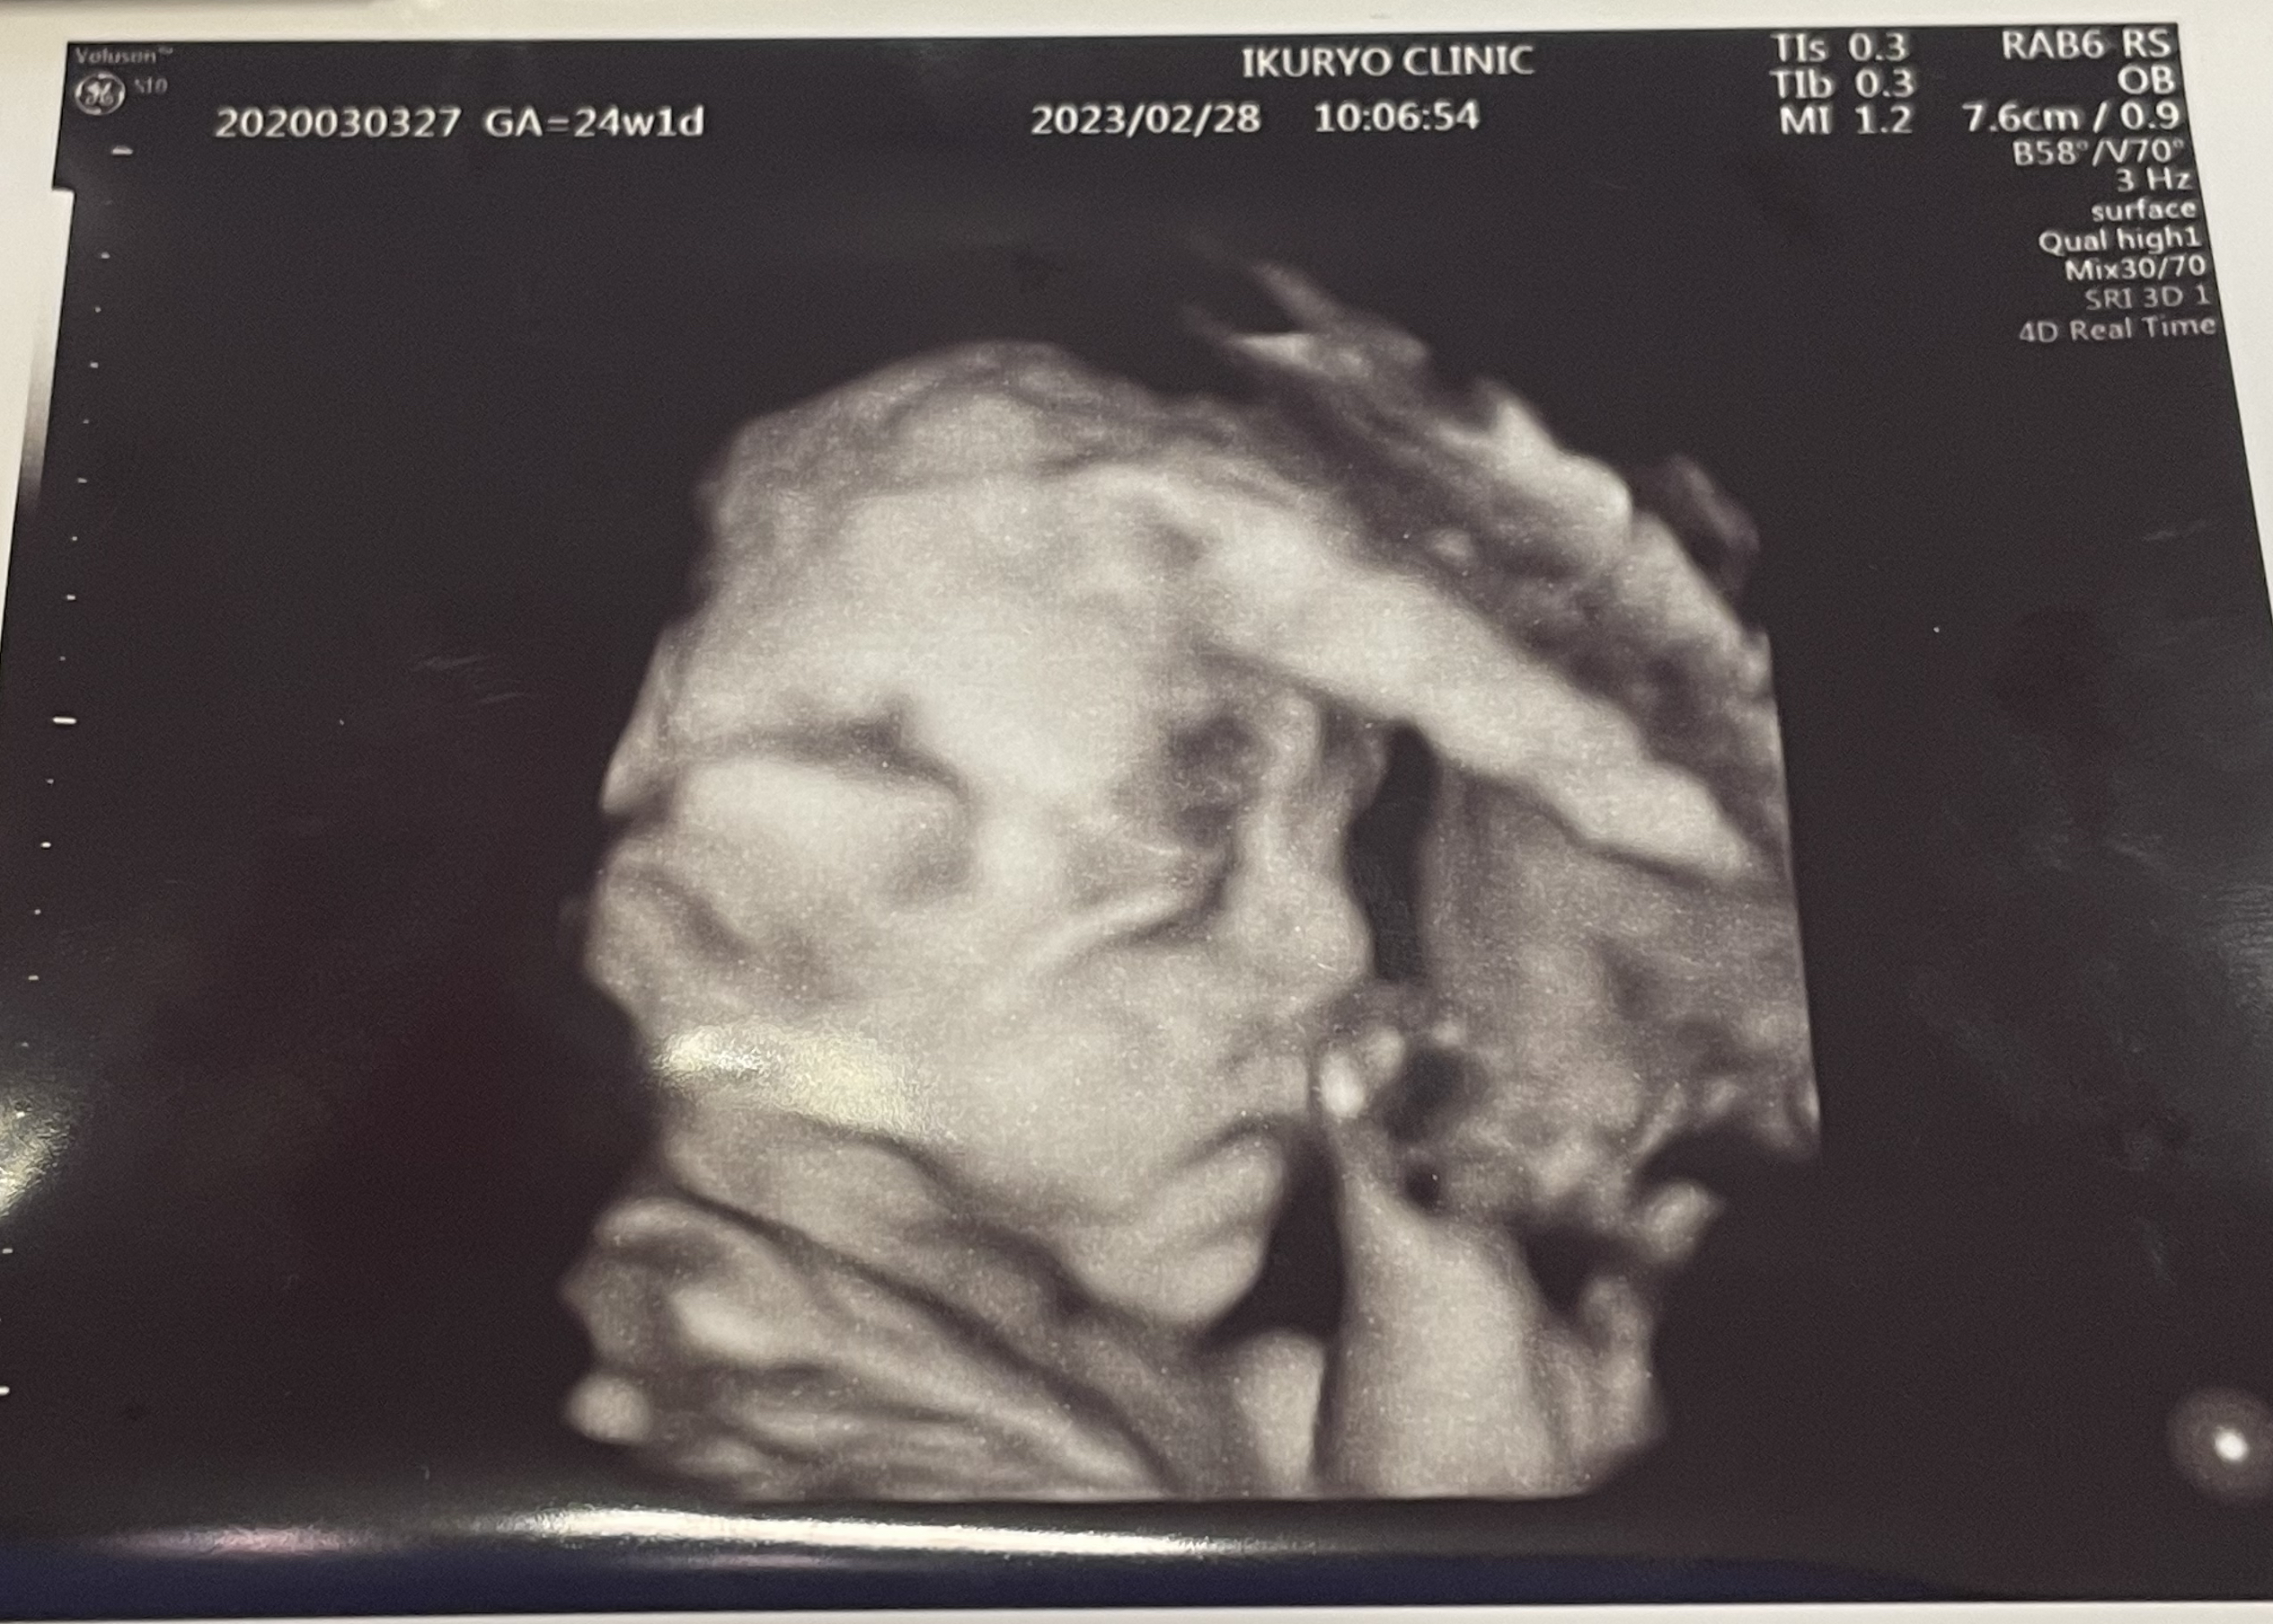

妊婦健診では、4Dエコーでお腹の中で成長したお顔を見られて感動しました。

今回の産院はオプションではなく、基本で4Dエコーがついていることに毎回驚きます。

エコーダイアリーというサービスと連携していて、エコーの動画を後から見たり、保存することもできます…。

だいぶ顔立ちがはっきりとしてきて、もうパパとママどちらに似ているか一目瞭然です!(パパ似)

息子はわたしにそっくりなのですが、息子の時の4Dエコー写真を見返してみると全体的にぺちゃっとしていて、お腹の中にいる時から今のおもかげがちゃんとあります^^ 笑

エコーをきっかけに思ったこと

健診中はもちろん動いた状態で見られるのですが、口を開けたり、手を動かしているところも見られるのがおもしろかったです。あくまでも健診なのでおもしろがるような楽しむようなことではないかもしれませんが、お腹にいる間からこうやって愛情が湧いてくるような出来事があるのって、育児放棄を防止したり、母になることへの不安解消にもつながるんじゃないかと思います。